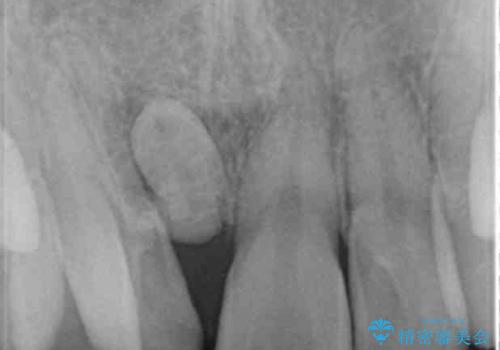

正中過剰埋伏歯で生じた前歯の審美障害 矯正治療での改善

- 前歯の見た目に悩まれて来院されました。

当初他院では、抜歯を行いセラミックブリッジを提案されていましたが、他の方法はないかと総合歯科治療を行う当院へと相談来院されました。

「時間がかかっても良いので、できれば歯を抜かずに矯正治療で治したい。」という強い希望があったので、矯正治療で歯並び・審美性の改善を計画します。